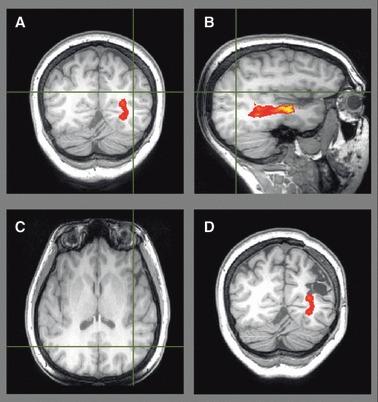

About one-third of patients with epilepsy are refractory to medical treatment and may be amenable to surgery. However, in patients with lesions on or near the presumed course of the optic radiation, the potential benefits of resection must be balanced against the risk of a visual field deficit. This study demonstrates the utility of diffusion tensor imaging (DTI) tractography in delineating the course of the optic radiation and its relationship to the epileptogenic lesion prior to epilepsy surgery.

Anatomic and DTI scans were acquired on 10 patients with medically refractory epilepsy undergoing presurgical evaluation at the National Hospital for Neurology and Neurosurgery. Five patients underwent surgery and repeat scans postoperatively. The optic radiation was delineated and visualized in relation to the lesions on anatomic images and in three-dimensional (3D) reconstructions. Preoperative and postoperative visual fields were acquired by Goldmann perimetry.

The entire optic radiation was reliably delineated bilaterally in all patients. The results provide helpful additional information in informing the patient of the risks of surgery and in planning the surgical procedure and approach. Postoperative imaging findings correlated with the visual field data.

The optic radiation shows significant anatomic variability, but can be reliably delineated by tractography. Because surgical disruption of the optic radiation has serious consequences for the patient, DTI tractography is a useful technique in this population. Future integration with real-time neuronavigation will minimize the risks of neurosurgery.